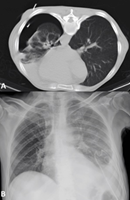

Percutaneous drainage by interventional radiology was proposed5-8 but could not be performed due to an iatrogenic pneumothorax during the procedure (Figure 4A, 4B).

Figure

4:

Complications of percutaneous drainage